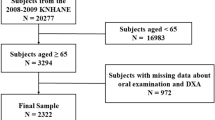

The study lasted two years and three months, with patient recruitment commencing in March 2008 and ending in June 2010. The patients' examinations were performed within two months of recruitment so that the data collection period was completed in August 2010. This was a cross-sectional study of volunteer subjects recruited from Manchester (UK) and the surrounding regions.

The eligibility criteria for the study were: female, aged between 45-68 years inclusive and who had undergone a dual energy X-ray absorptiometry (DXA) scan of the proximal femur and lumbar spine in the previous three months at one of two hospital sites. Patients were initially identified from the databases held at both hospitals. The exclusion criteria were: individuals who had a medical condition that made it impossible for them to brush their own teeth (as in stroke, paralysis etc), leukaemia, diabetes, chemotherapy and those taking intravenous bisphosphonates. If patients fulfilled the inclusion and exclusion criteria they were sent an information leaflet and were invited to participate in the study. Ethical approval was granted (Number 07/Q1402/58) and informed consent obtained.

Recruitment of 398 subjects was achieved during the course of the study. Of these, DXA data were accessible for 380. Dental radiographic and clinical information was available for 359 patients but, of these, radiographs of two subjects were non-diagnostic and thus discarded. A complete set of DXA data, clinical information and dental radiographs were available for 333 subjects, of whom 90 (27%) were classified in the osteoporosis group and 243 (73%) as having normal BMD. Table 1 shows the characteristics of the two groups.